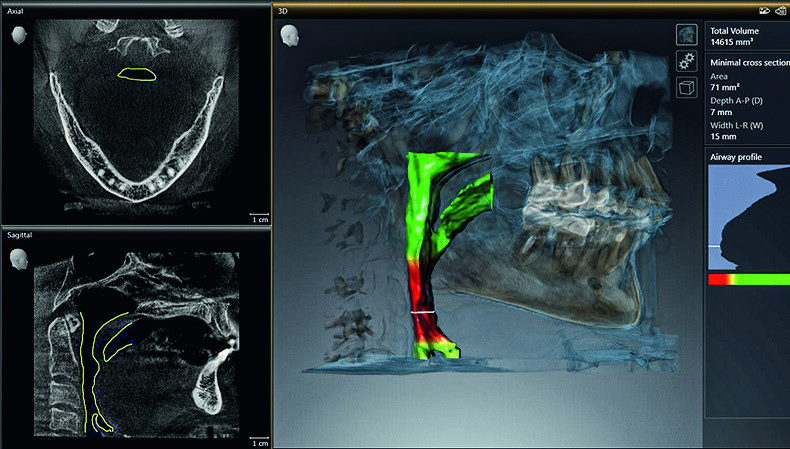

The patient had dental signs and symptoms of sleep apnea, including a narrow arch form, a scalloped tongue, clenching and a narrow airway. Viewing the Orthophos SL 3D scan in SICAT Air (Fig. 1) helped the patient to better understand the connection between the upper airway and dentistry. The next step involved a home sleep study that, indeed, revealed moderate sleep apnea.

Fig. 1: Upper airway visualized in SICAT Air. (Images: Dentsply Sirona)